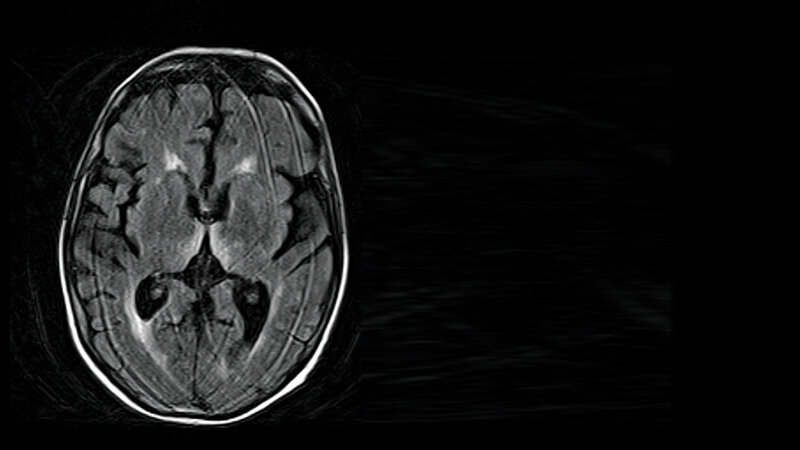

Dieser Artikel gibt einen Überblick über die toxischen Folgen von Alkohol auf das Herz, das Gehirn, das Herz-Kreislauf-System sowie das Nervensystem.

Schlüsselwörter: Alkoholkrankheit, alkoholische Kardiomyopathie, Wernicke-Korsakow-Syndrom